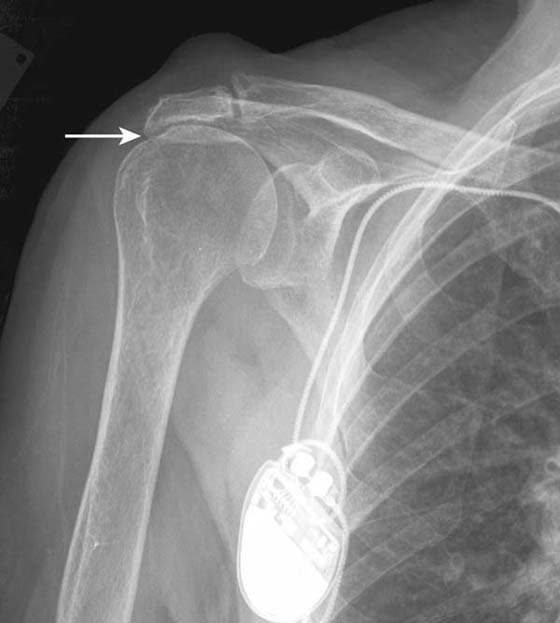

Although shoulder impingement is a clinical diagnosis, it has imaging manifestations that are helpful in guiding treatment. Radiography plays a role in the initial examination of impingement. Subacromial spurs, glenohumeral joint osteoarthritis, and evidence of chronic rotator cuff tear with a high riding humeral head may be identified with radiographs,5 which may further influence management decisions (Fig. 14-6). Noncontrast shoulder MRI is frequently employed in the assessment of impingement. Manifestations of impingement, such as subacromial spur, subacromial/subdeltoid (SASD) bursitis, and rotator cuff tears, are all easily demonstrated on MRI.15-17 Features of a rotator cuff tear that can be assessed on MRI include tear type (full vs. partial thickness), tear location, tear dimensions, tear morphology, tear gap/degree of tendon retraction, and the presence of rotator muscle atrophy (Fig. 14-7).

images

Figure 14-6 Chronic rotator cuff tear. Anteroposterior radiograph of the shoulder demonstrates severe narrowing of the acromiohumeral distance (arrow), indicating chronic rotator cuff tear. Marked subacromial spur formation is also seen. An MRI was contraindicated in this patient due to the presence of a cardiac pacemaker.